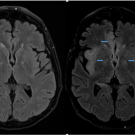

02/12/2019

A 68-year-old woman presented to the emergency department at an outside hospital with weakness, slurred speech, confusion, polyuria, and diarrhea. She had been in her usual state of health until a week...